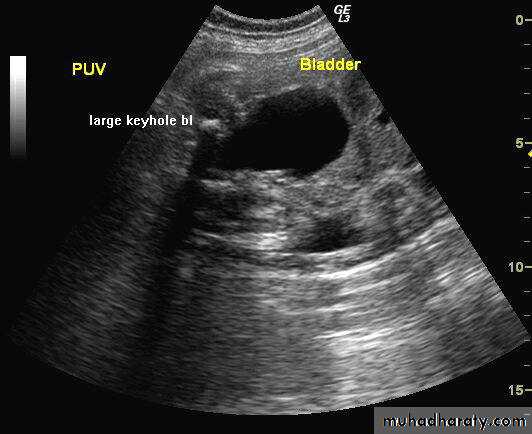

Approximately ½-2/3of boys with PUV will be suspected prenatally. Prenatal findings on ultrasonography in suspected cases may include:

a thick walled bladder, the ‘keyhole’ sign with a dilated bladder and posterior urethra, unilateral or bilateral hydroureteronephrosis, echobright kidneys and oligohydramnios.

US : Keyhole sign